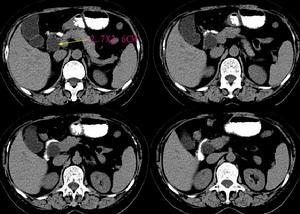

3.超聲檢查B型超聲為非侵入性檢查,可以早期發現葡萄胎組織侵入子宮肌層程度,協助診斷子宮內滋養細胞腫瘤病灶。宮壁顯示局灶性或瀰漫性強光點或光團與暗區相間的蜂窩樣病灶,應考慮為侵蝕性葡萄胎或絨癌。

4.組織學診斷單憑刮宮標本不能作為侵蝕性葡萄胎的診斷依據,但在侵入子宮肌層或子宮外轉移的切片中,見到絨毛結構或絨毛退變痕跡,即可診斷為侵蝕性葡萄胎。若原發灶與轉移灶診斷不一致,只要任一標本中有絨毛結構,即應診斷為侵蝕性葡萄胎。